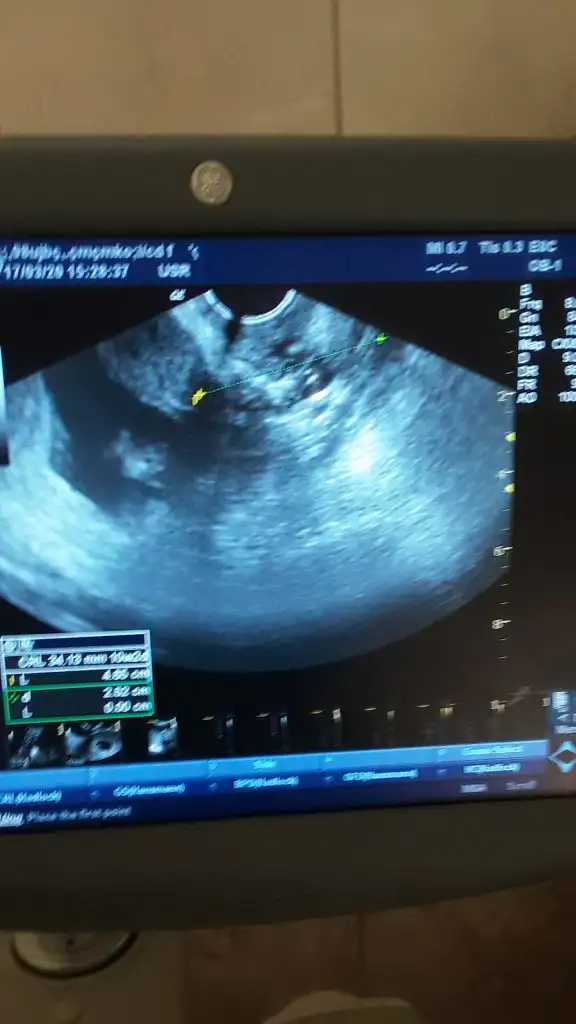

Bunlar bu günden en son da belli etmemişti yine belli etmemiş mi bakalım:)

Eklentiler

• 20200317_145448.webp

20200317_145448.webp

14,3 KB · Görüntüleme: 37

• 20200317_145431.webp

20200317_145431.webp

27 KB · Görüntüleme: 25

• 20200317_145415.webp

20200317_145415.webp

16,3 KB · Görüntüleme: 35